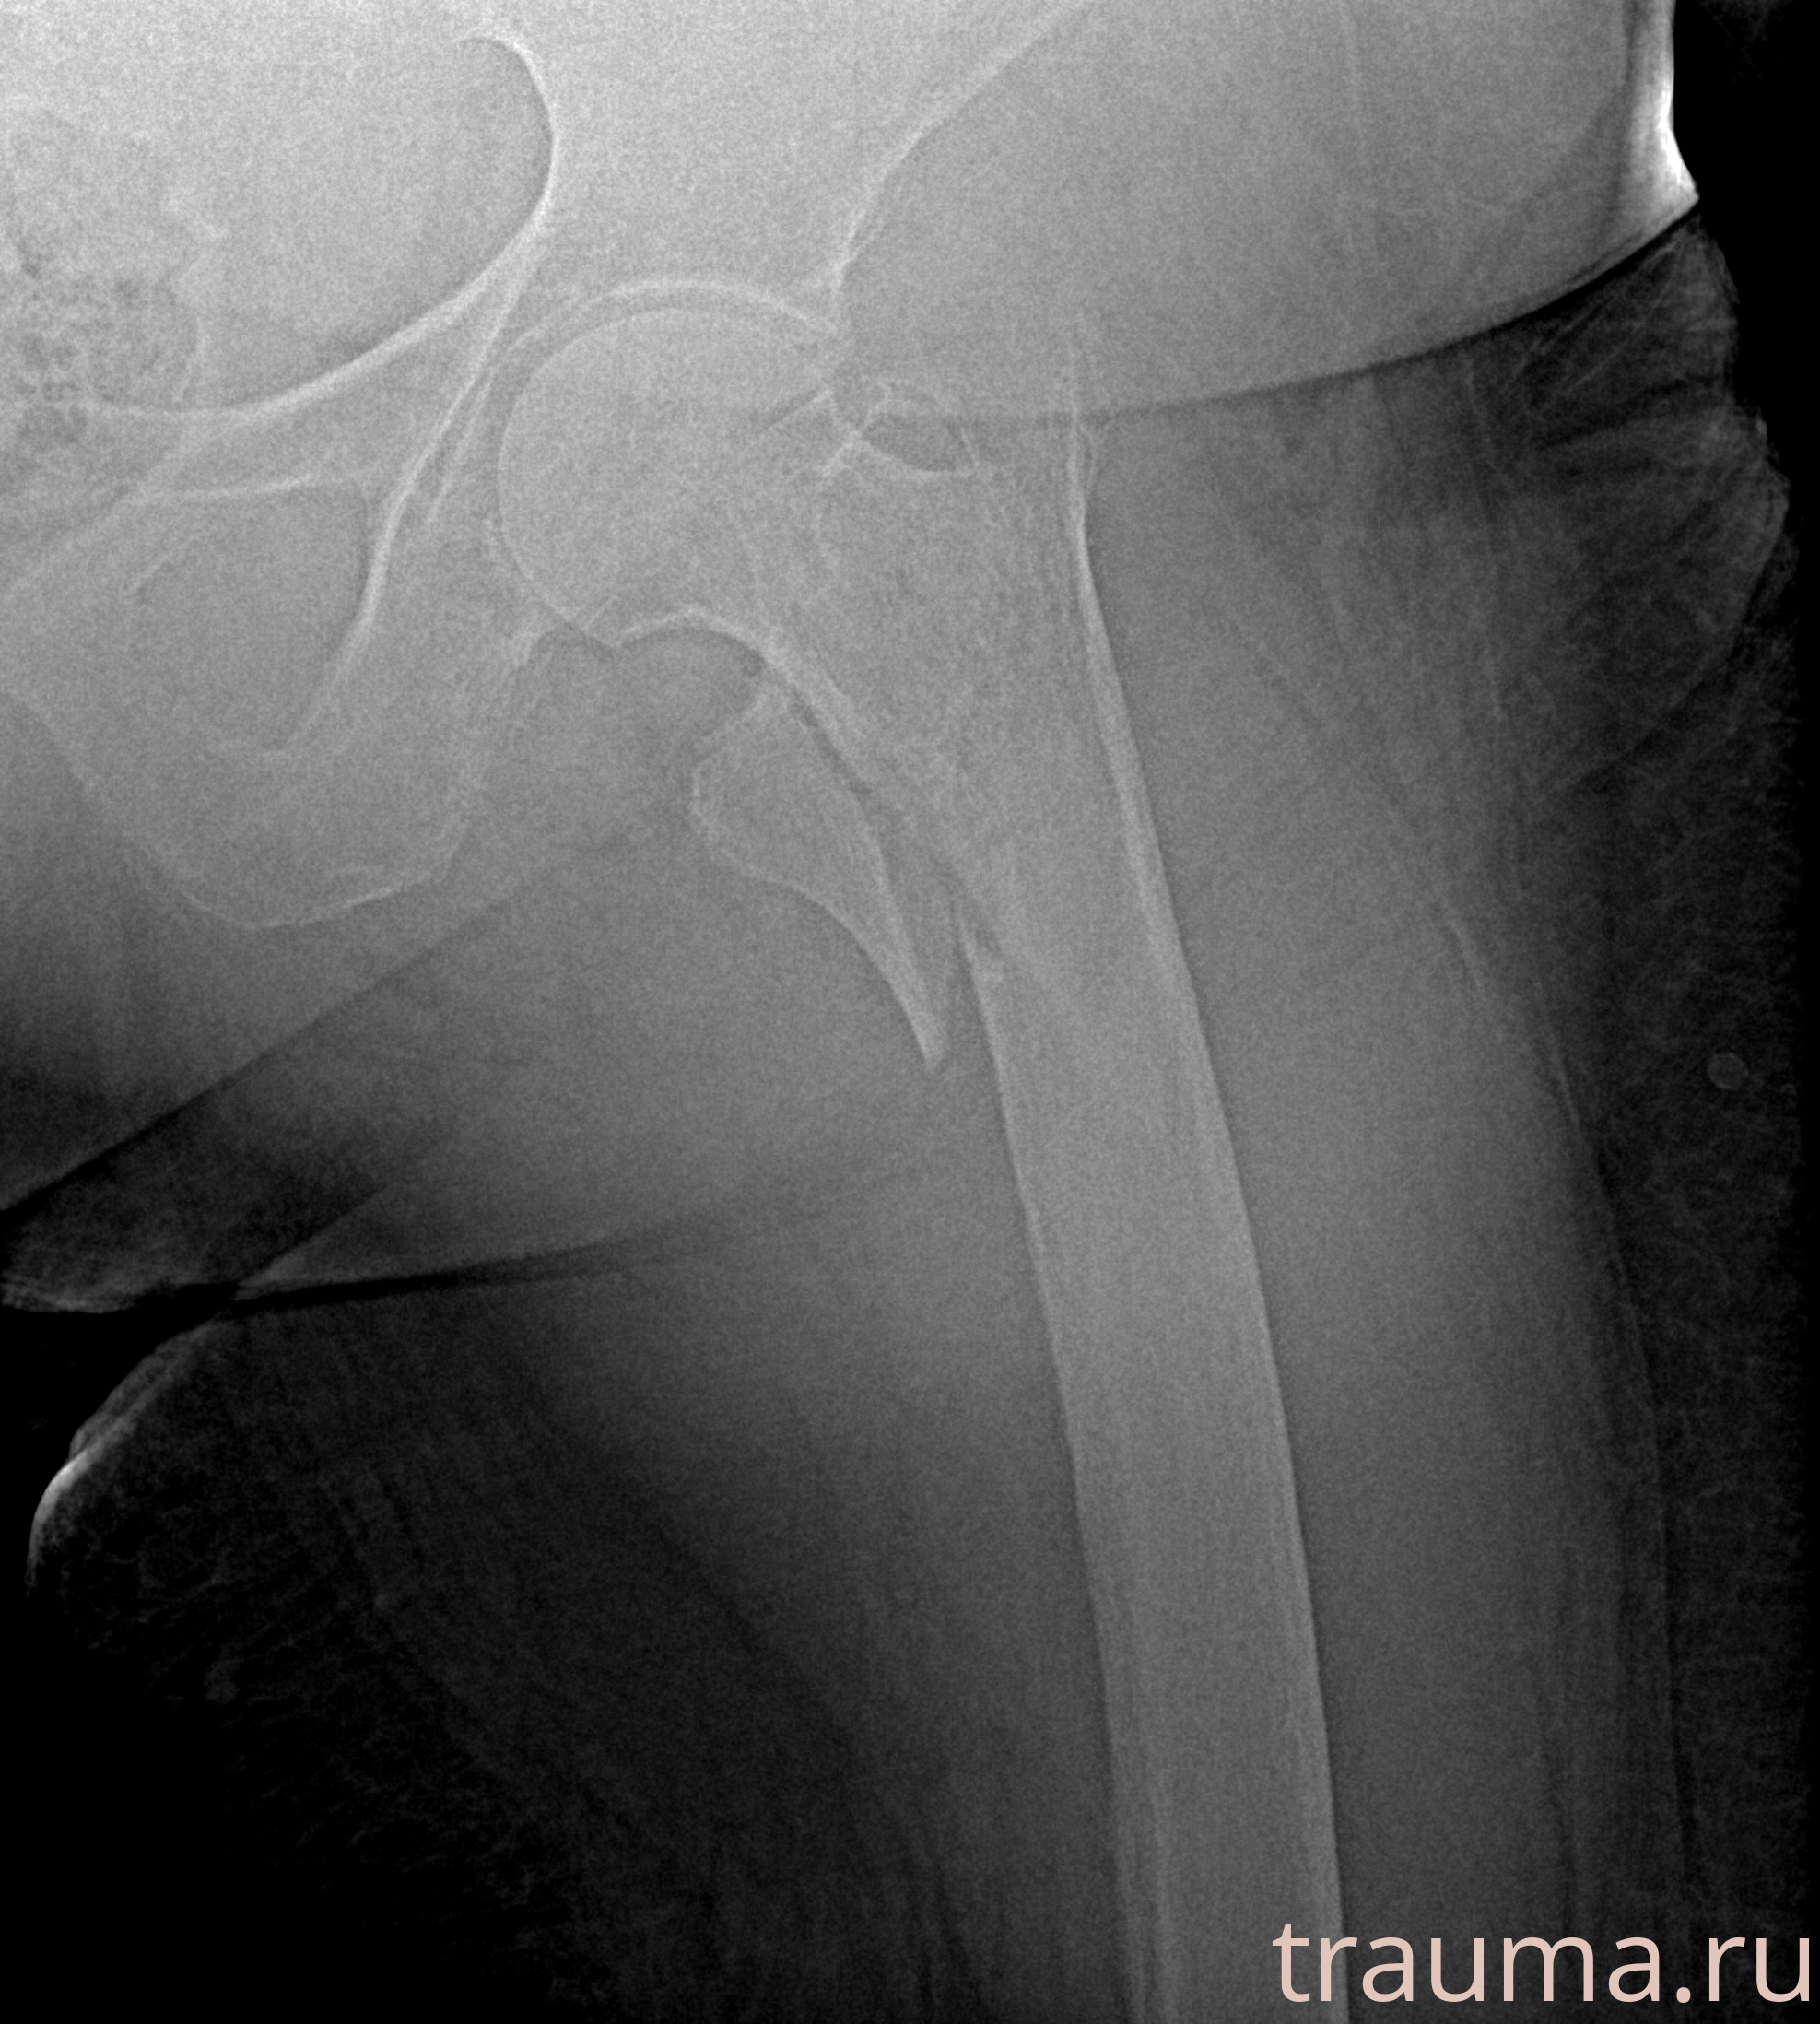

Первая помощь при переломе шейки бедра

Рентген на дому: по вашему адресу приезжает врач-рентгенолог, травматолог-ортопед с мобильным рентгеновским аппаратом, проводит диагностику травмы или заболевания, делает необходимые рентгенограммы, дает рекомендации по дальнейшему лечению. Получить качественные снимки в домашних условиях возможно благодаря уникальной методике, разработанной МосРентген Центром для института  Склифосовского